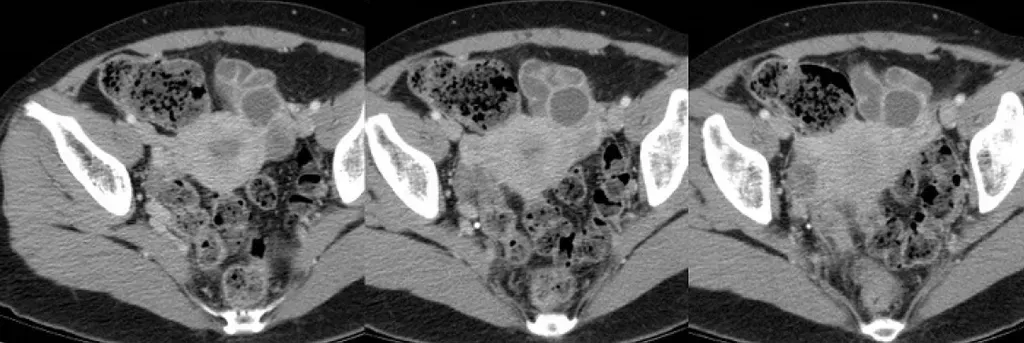

【112-2 醫學(六) 第72題】26歲女性病人,因下腹痛及發燒接受電腦斷層檢查(如附圖)。最可能之診斷為何?

詳解

破題關鍵

這張電腦斷層影像顯示骨盆腔內有一個複雜、多房性且周圍發炎明顯的病灶,結合病人有下腹痛和發燒的症狀,最符合感染性膿瘍的表現。